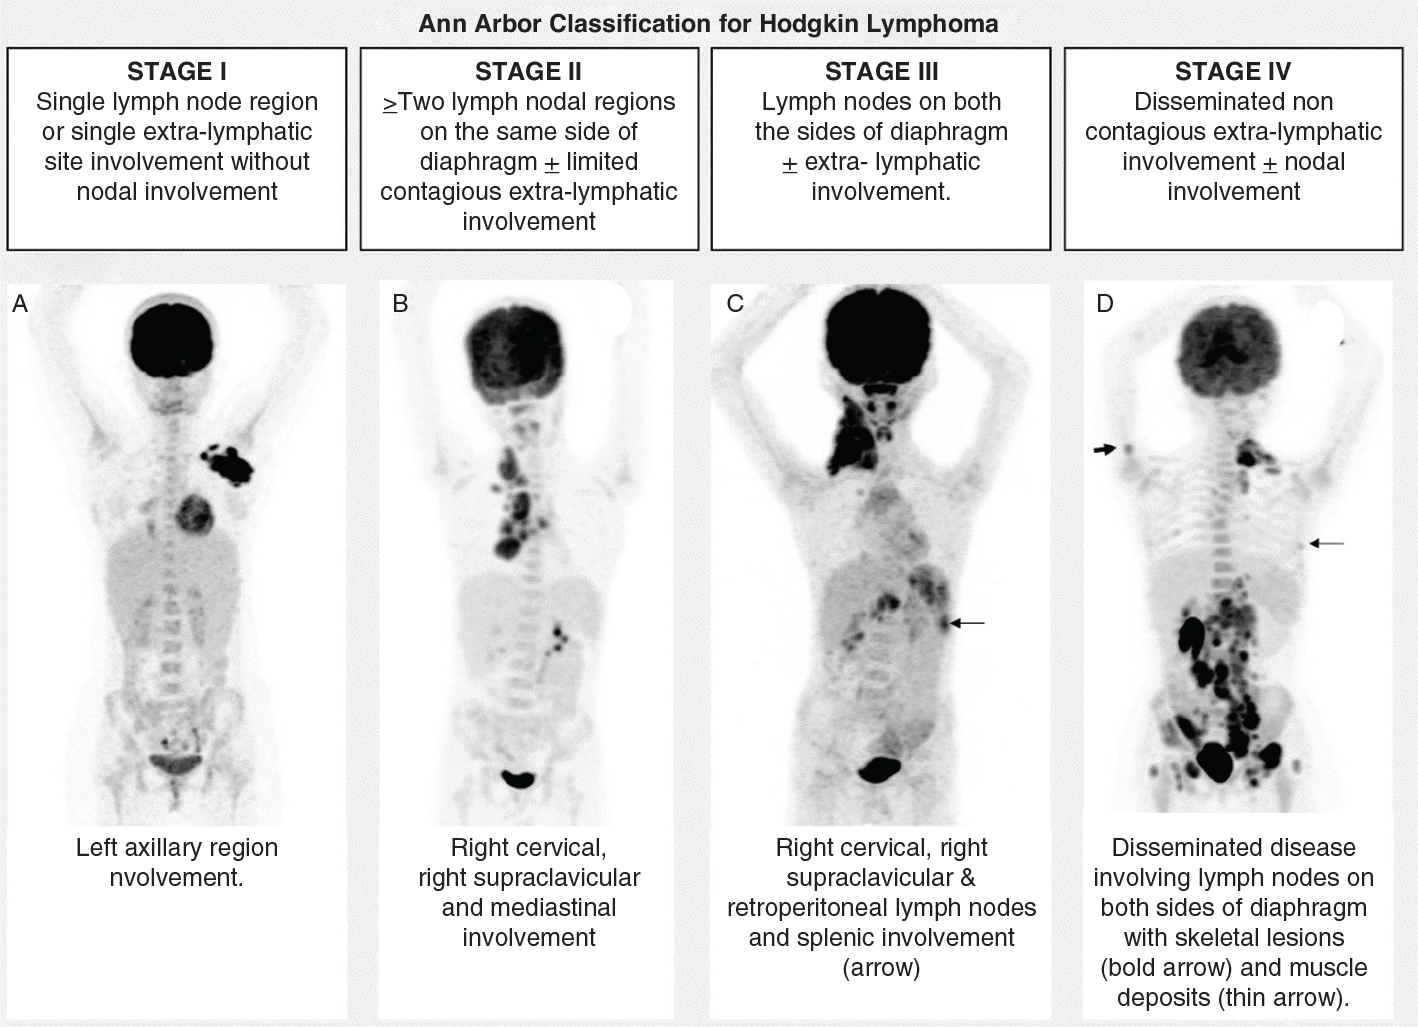

FDG-PET/CT showed superior sensitivity and specificity when compared to traditional staging techniques (USG, CT, MRI and bone scintigraphy), i.e. 96.5–98% versus 77–87.5% and 96.5–100% versus 60–98.7%, respectively (11, 12). Furthermore, the initial staging of disease with PET/CT is essential for risk stratification and accurately defining the extent of potential radiation treatment fields when radiotherapy is anticipated. National comprehensive cancer network (NCCN) guidelines recommend an initial staging workup 2–4 weeks before therapy with an FDG-PET/CT or PET/MR (with CT chest to rule out lung involvement) having diagnostic quality contrast-enhanced CT or MR when available Staging of pediatric HL and NHL follows different staging classifications. The active pediatric HL trials such as the European Network for Pediatric Hodgkin Lymphoma, Clinical Trial 2 (EuroNet- PHL-C2) and Children’s Oncology Group (COG) use the Lugano modification of the Ann Arbor staging system (Figure 1). However, pediatric NHL staging follows the International Pediatric Non-Hodgkin Lymphoma Staging System (Figure 2). The positive lesion definition in pediatric lymphoma is different from the Lugano criteria, which uses an adult cut-off of size, which is larger than they are for children, and hence NCCN gives the following protocols for the site involvement based on their panel consensus; however, it is an area for research:

Fig 1

Figure 1. MIP FDG-PET. Ann Arbor classification for HL with examples showing maximum intensity projection (MIP) images of FDG-PET.